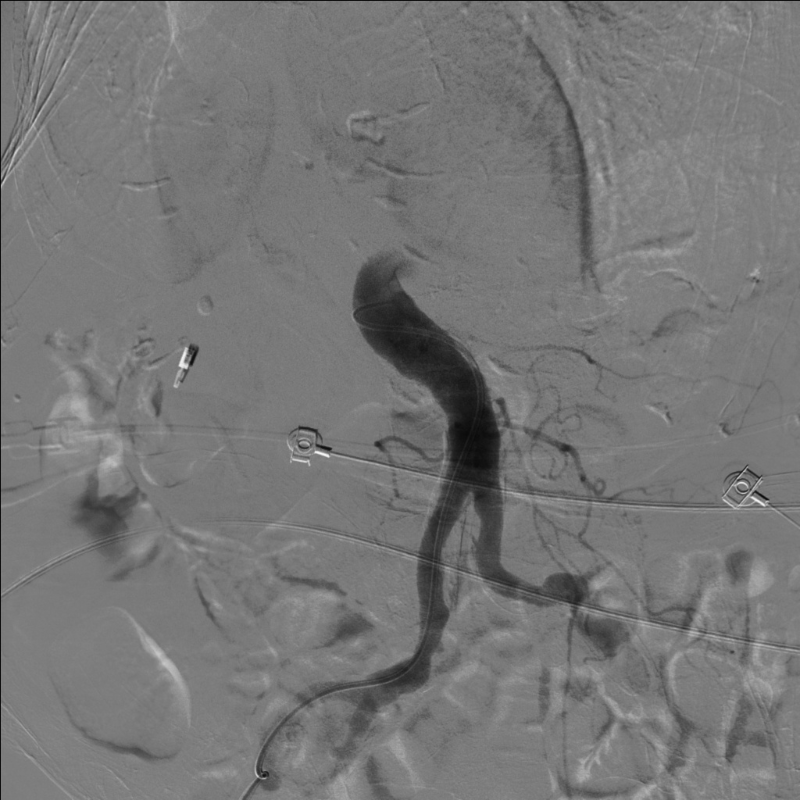

經微導管注入栓塞劑到胃十二指腸動脈全程,造影顯示胃十二指腸動脈栓塞徹底,肝內動脈分支血運良好無副栓塞。

術后,患者送往重癥醫學科行監護、支持對癥治療。通過治療,患者血壓正常,無需使用升壓藥物,無嘔血,黑便逐漸減少,血紅蛋白穩定,血肝腎功能正常,恢復良好。